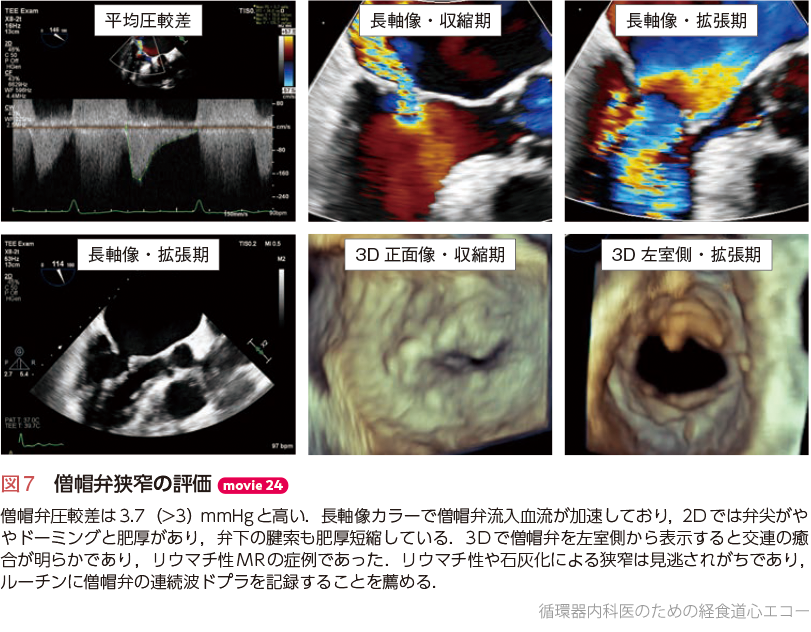

2024年 お歳暮・冬ギフト特集 実践3D心エコー図法 医学一般